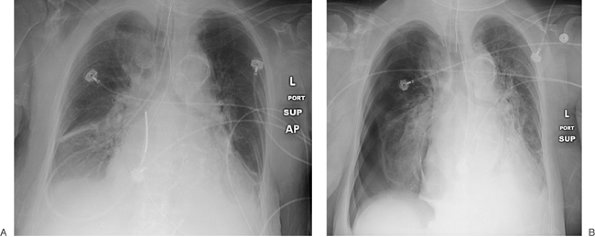

Numerous types of single- and dual-lead pacemakers and combination pacer–defibrillators are available. They are used to treat a variety of dysrhythmias. Accurate interpretation of their appearance on chest radiography requires knowledge of the specific type of pacemaker placed. The three major approaches to insertion of a pacemaker electrode into the heart include epicardial, subxiphoid, and transvenous implantations; transvenous is the most common. With single-lead pacers, the wire is placed into the right ventricle by way of the cephalic, subclavian, or jugular vein. When the lead is wedged into the myocardial trabeculae near the cardiac apex, the lead will be stable and have maximal contact with the endocardial surface. With dual-lead pacers, one lead is generally placed into the right atrium and the other into the right ventricle. It is important to know where the desired placement of leads is for each patient, because placement within the coronary sinus may be accidental or purposeful. After the electrodes are positioned, the generator is placed in a pouch in the subcutaneous tissues of the chest wall or beneath the pectoralis muscle. Biventricular pacemakers are used to treat congestive heart failure. Leads are placed in the right atrium and right ventricle, and a third lead is placed in the coronary sinus for pacing the left ventricle (Fig. 5-18).

FIGURE 5-18. Biventricular pacer. PA (A) and lateral (B) chest radiographs show normal positioning of lead tips in the right atrium (solid white arrow), right ventricle (dashed white arrow), and coronary sinus (solid black arrow).